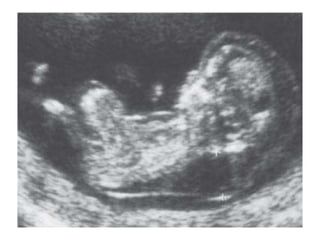

Fetal Böbrekler

Fetal böbrekler ve

mide görülmekte

12-13. haftada mide

mutlaka izlenir

Her iki ekstremite